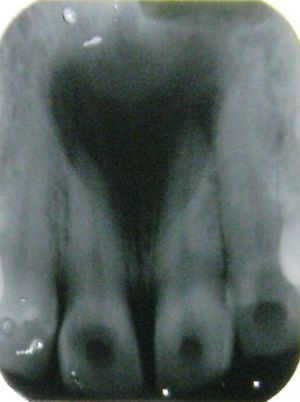

The nasopalatine duct cyst (abbreviated NPDC) occurs in the median of the palate, usually anterior to first molars. It often appears between the roots of the maxillary central incisors. Radiographically, it may often appear as a heart-shaped radiolucency This cyst arises from the remnants of the nasopalatine duct ,an embryonic structure connecting the nasal and oral cavities in the area of the incisive canal